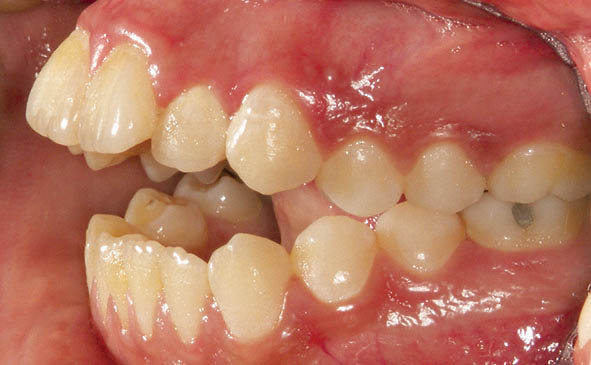

شکل 38-3

شکل 39-3

شکل 40-3

شکل 38-3 الی 40-3: اپن بایت شدید